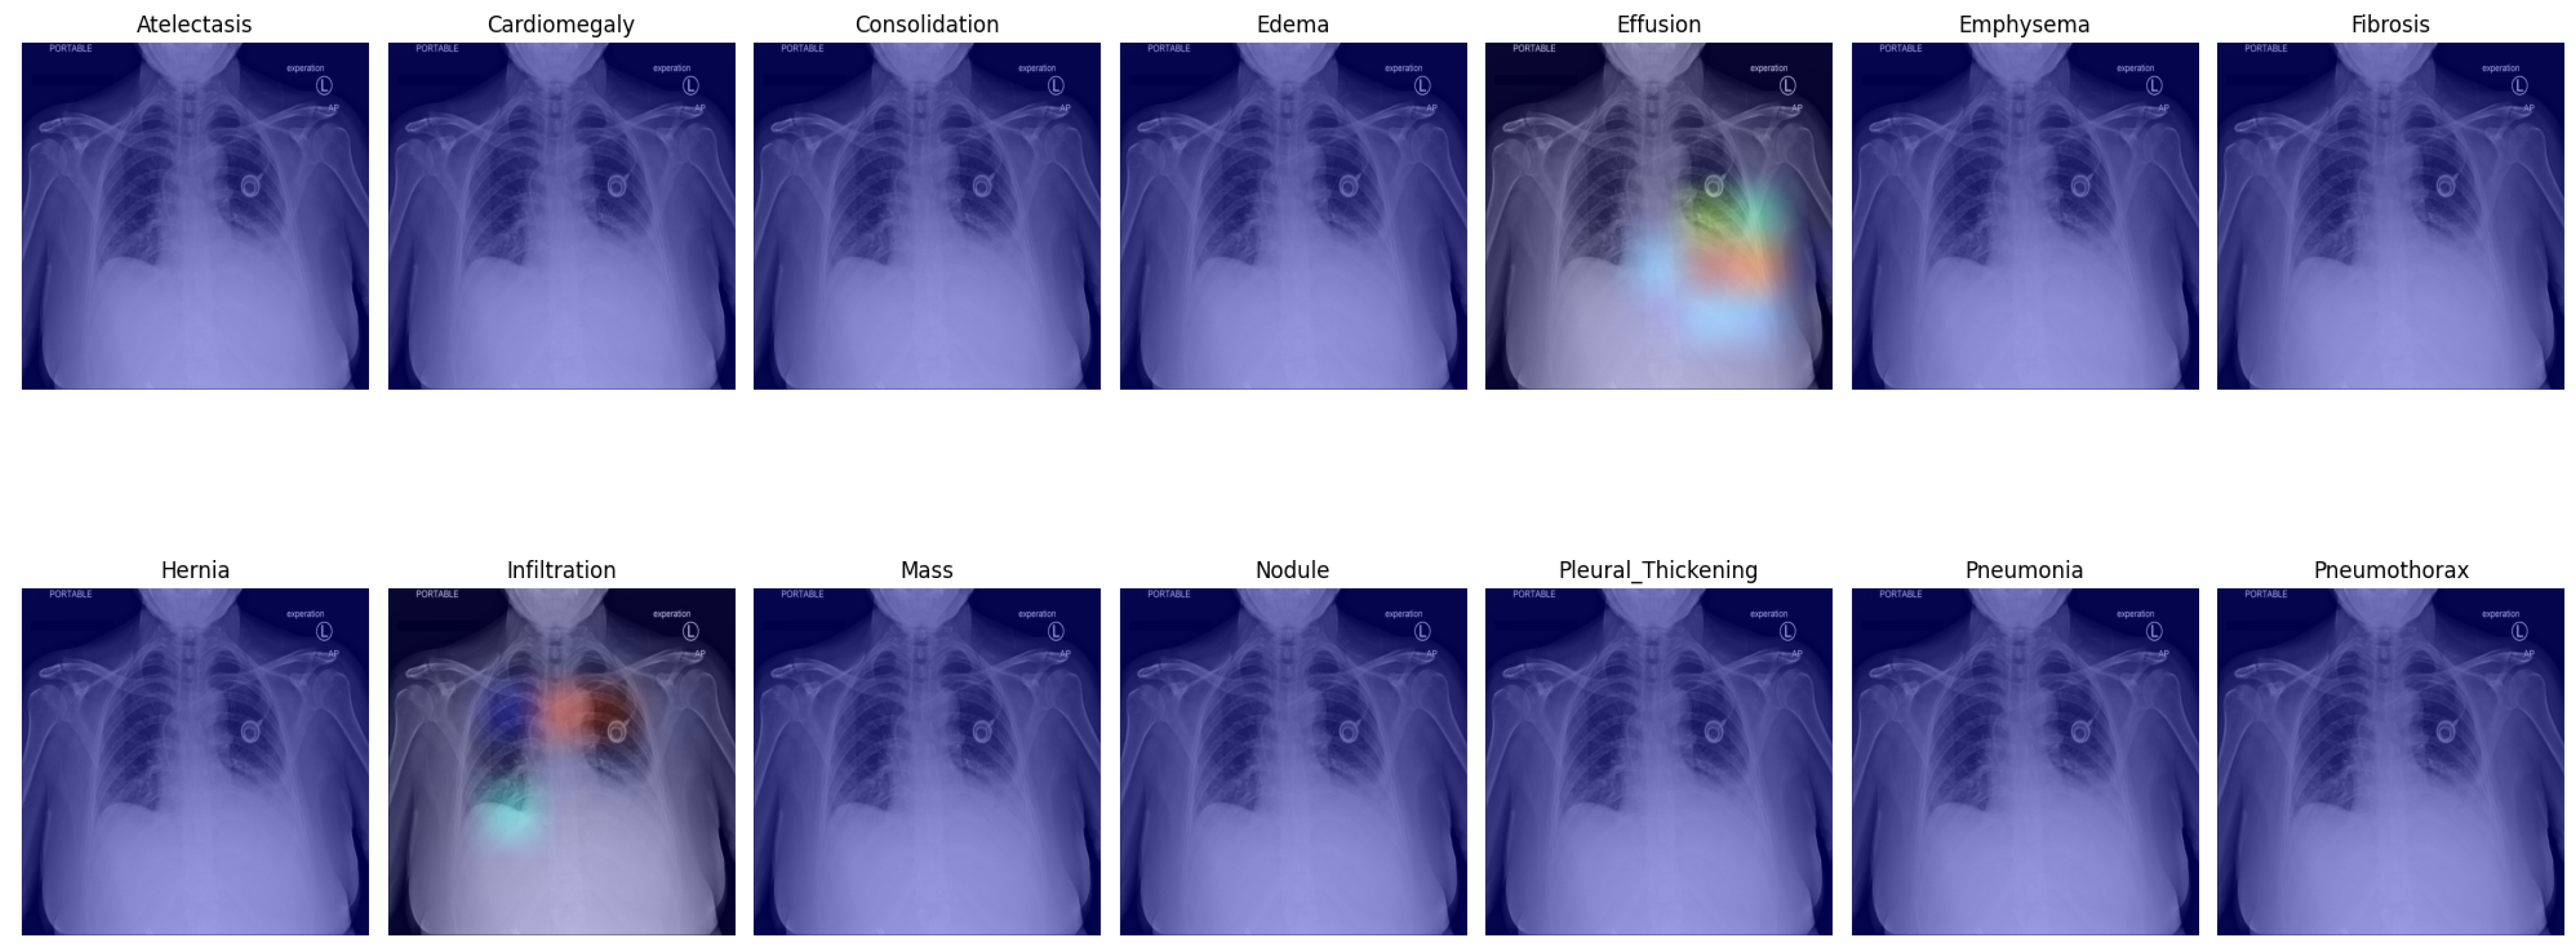

3.5. Visual Representation

In this section, we present a visual interpretation of the learned features, using the Gradient-weighted Class Activation Mapping technique (Grad-CAM) [33]. Grad-CAM offers a technique to produce “visual explanations” for decisions from a broad array of CNN-based models, enhancing their transparency and interpretability. Grad-CAM utilizes the gradients of any target concept (e.g., ‘Effusion’ in the current context) flowing into the final convolutional layer to generate a coarse localization map. This map highlights the crucial regions in the image for predicting the concept [33]. Unlike prior methods, Grad-CAM can be applied to various CNN architectures without the need for re-training or architectural modifications.

Figure 4 presents the default classifier head. In the first picture in the first row, atelectasis was mistaken due to overlapping rib arches. Since the left hemidiaphragm was obscured by the enlarged cardiac shadow, effusion in the fifth image in the first row is marked below the expected level of the diaphragm (blue). In the sixth image in the first row, emphysema was suggested, probably due to the significant difference in the overall density of the lung bases. In the third picture in the second row, the enlarged aortic knob was mistaken for a mass. In the seventh picture in the second row, pneumothorax was suggested in the right apex. This area is often difficult to assess for junior radiologists; as the bronchovascular pattern is faint, it can raise a false suspicion of pneumothorax.

Figure 4. Grad-CAM of model with the default classifer.